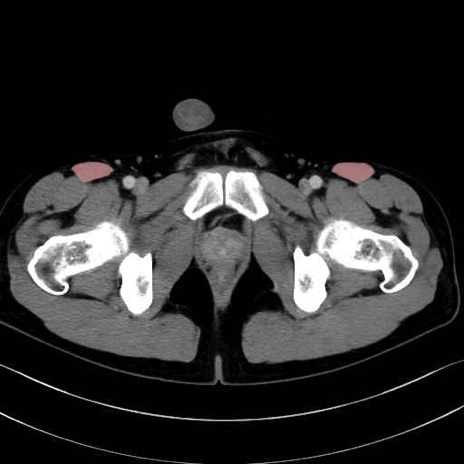

縫工筋 (Sartorius)